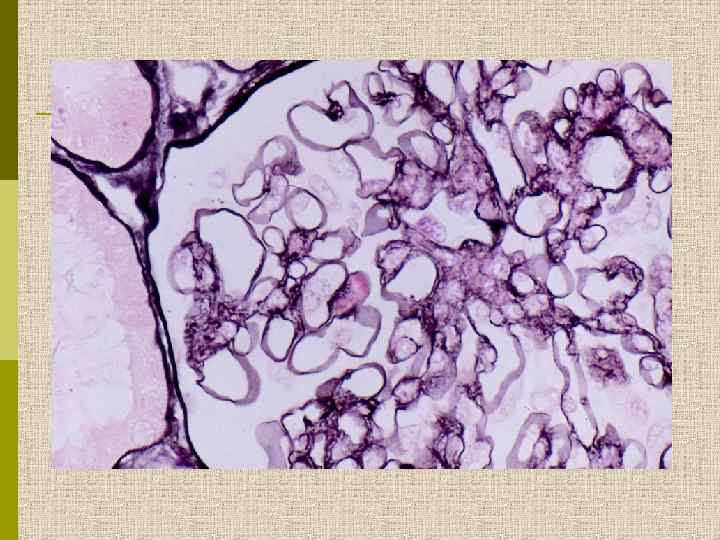

Мезангиопролиферативный гломерулонефрит (расширение мезангия + пролиферация мезангиоцитов)

Мезангиопролиферативный гломерулонефрит. Выраженная мезангиальная пролиферация и расширение мезангиального матрикса ( PAS)